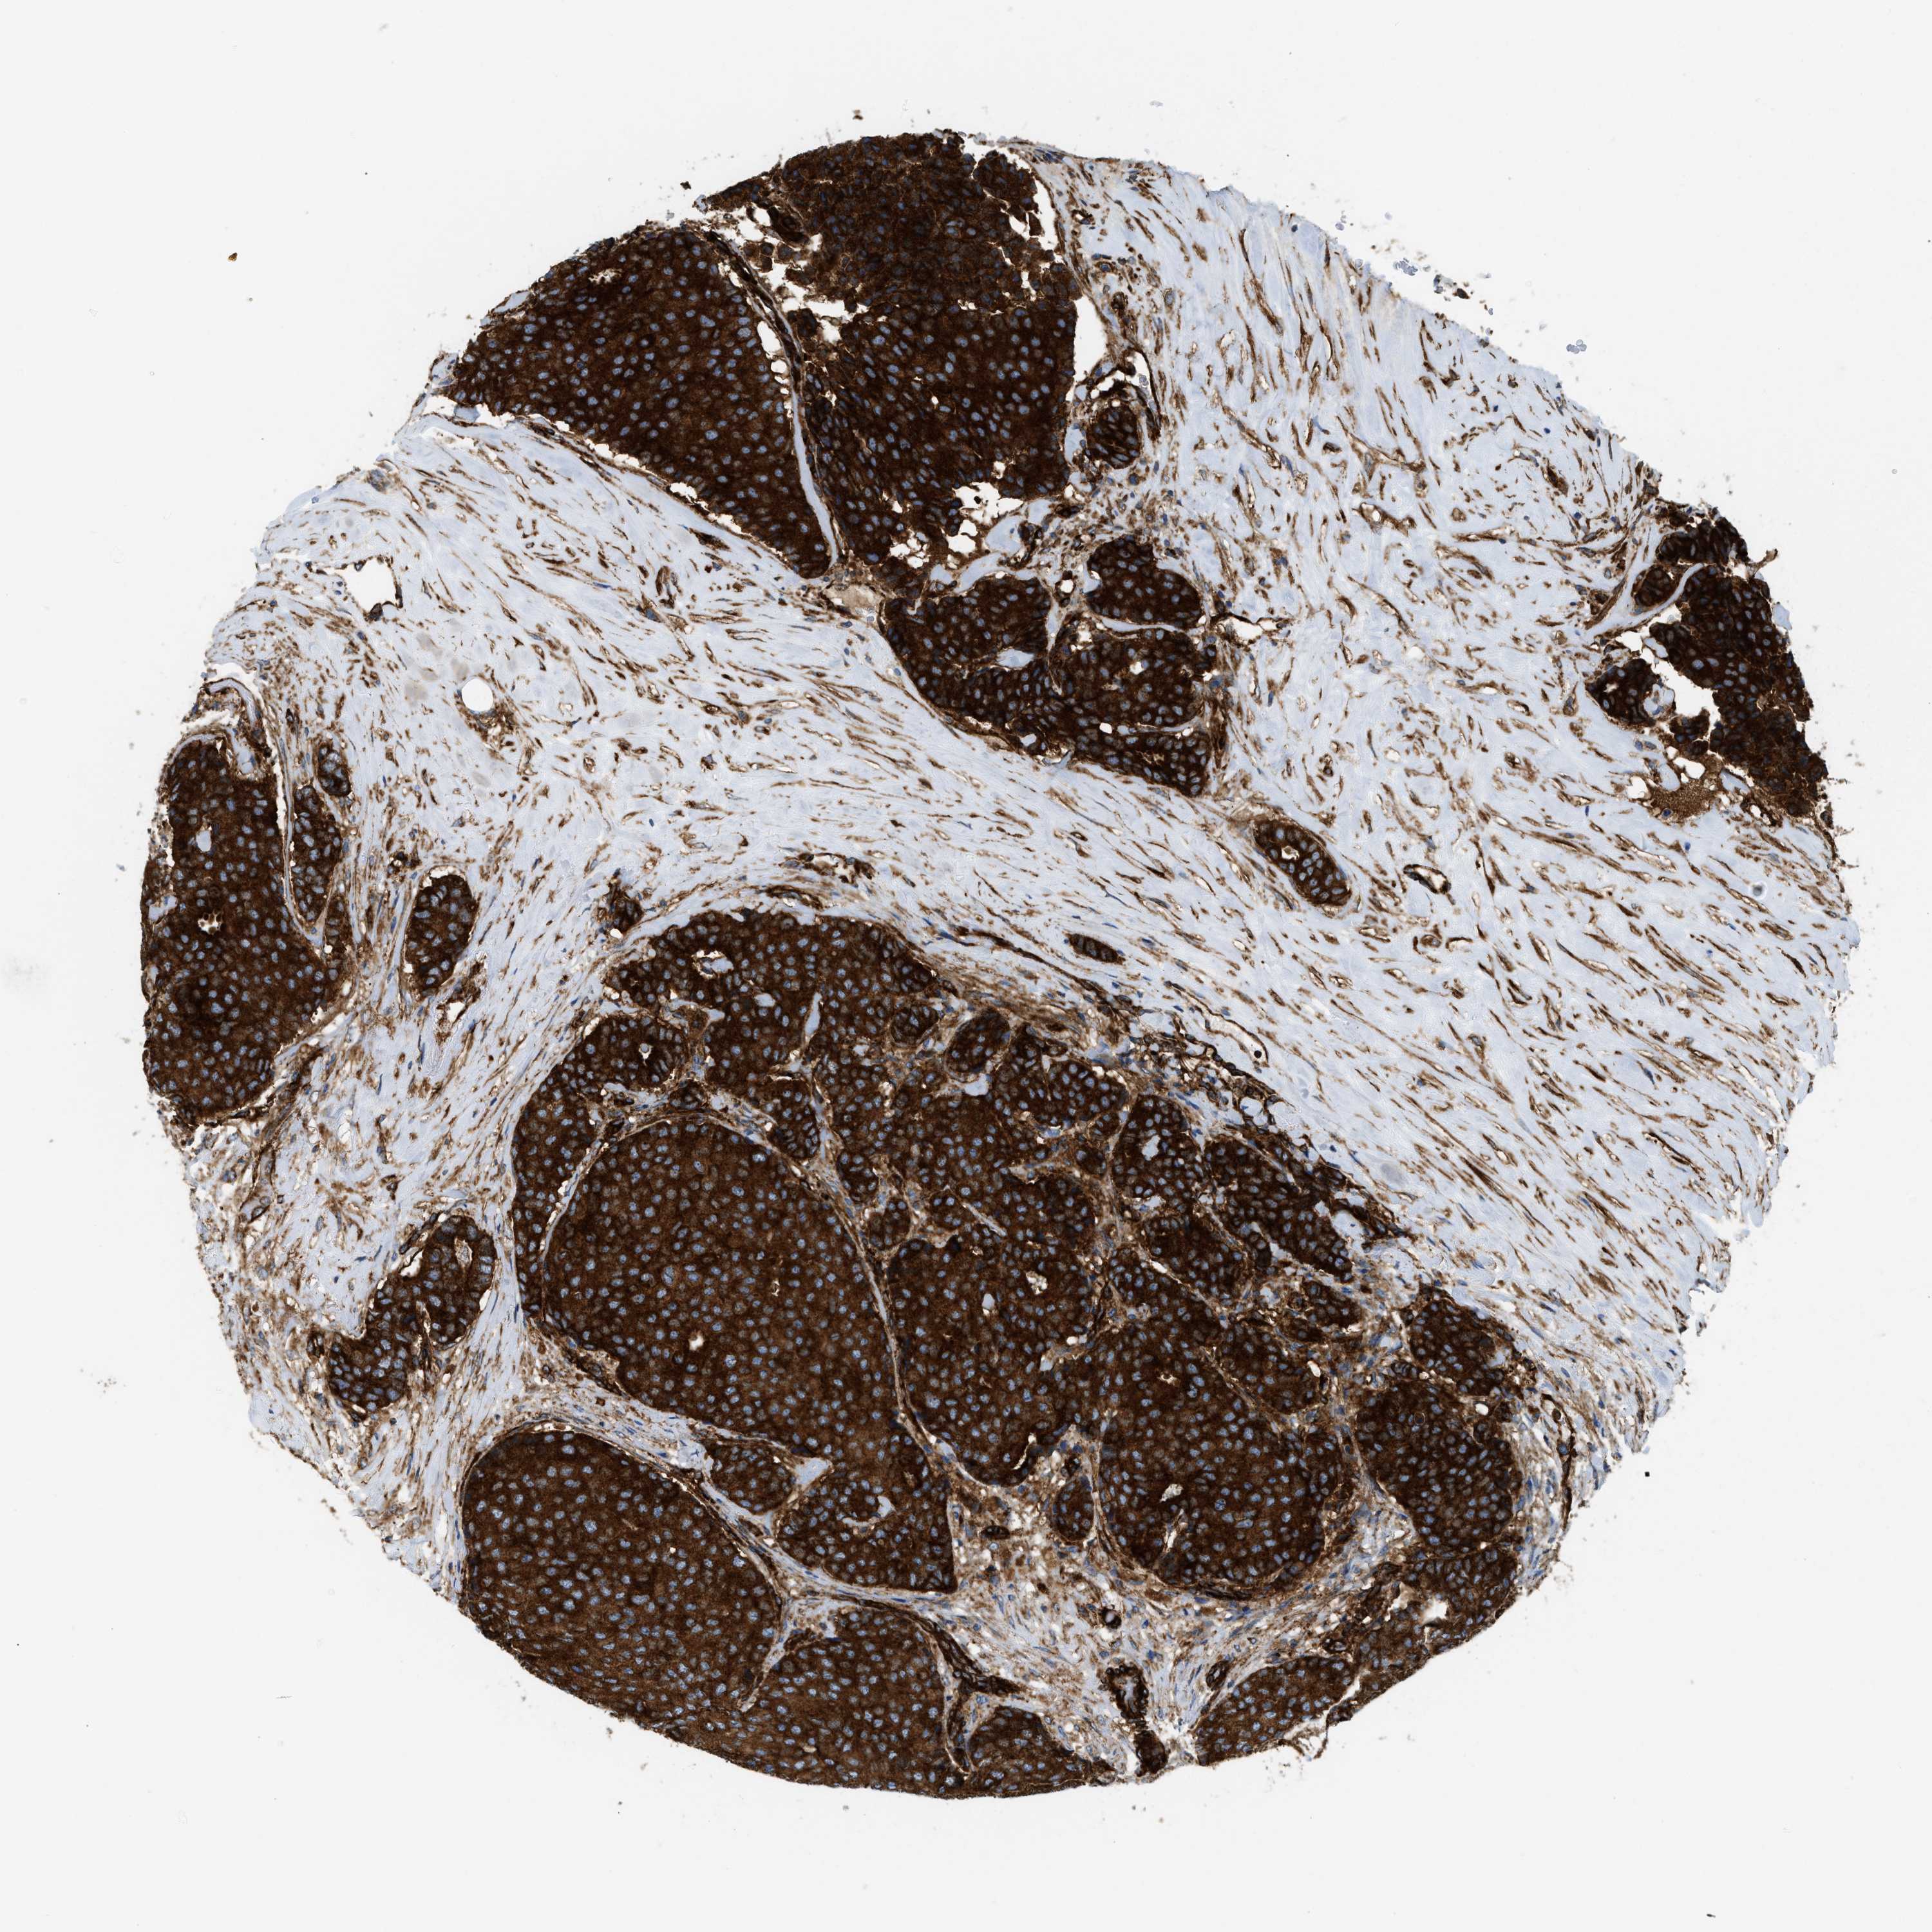

CANCER BREAST CANCER Show tissue menu

BRCA TCGA BRCA VALIDATION PROTEIN EXPRESSION